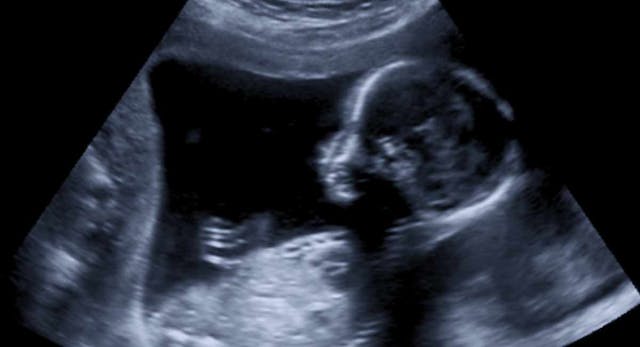

Fetal Development

Facts about fetal development that were known at the time of Roe’s passage

Early abortion kills a human being

Listen to fetal heartbeats as young as five weeks

Video: Fetal development week by week